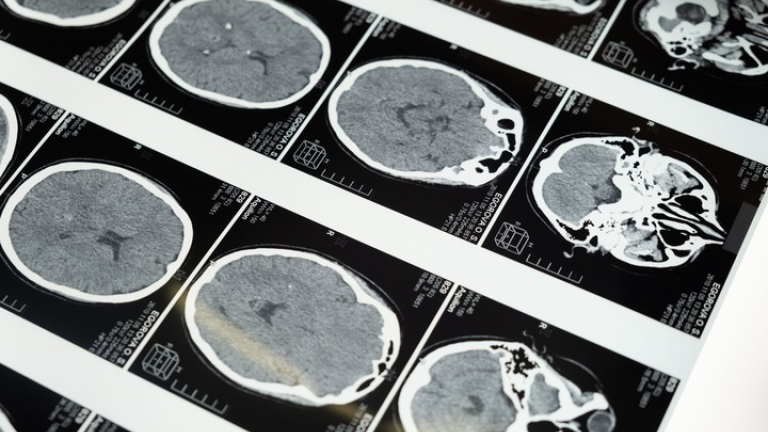

De hecho, aquí podría estar la clave. No en el número de neuronas, sino en lo óptimas que sean las conexiones entre ellas. Es, de acuerdo con Dierssen, lo que diferencia a las personas que destacan por un talento sobresaliente: tienen un patrón de conectividad entre las distintas áreas cerebrales mucho más activo que la media de la población.